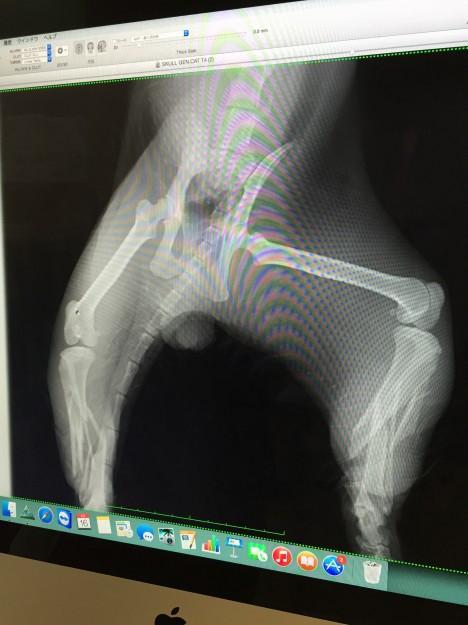

しかも骨盤まで折れていました。

レントゲンで見たらバキバキに折れていました。

それだけじゃなく、頭蓋骨骨折と思っていた場所。

調べてみると下アゴの付け根が折れていて、頭蓋骨が動いていたようです。

しかも、上アゴの骨まで折れていて、プレート状の骨が上口を突き破り口の中から骨が出てきています。